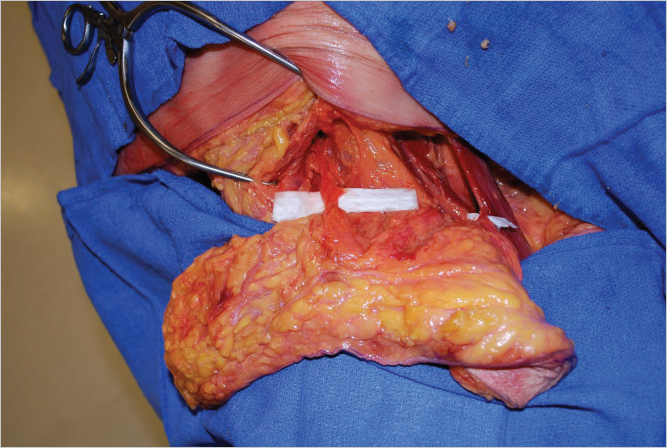

The proximal femoral artery gives rise to the profunda femoris system supplying branches to the adductor muscle group of the thigh as well as the overlying skin. Cadaver injection studies and computed tomography (CT) angiography demonstrate that the dominant blood supply to the posterior thigh arises from posterior perforators emerging from the profunda femoris artery (▶Fig. 58.2).

With the midline and inferior gluteal crease as reference points, the largest, most well-placed perforators with the longest vascular pedicle can be identified. In this image, the best perforators have been identified as R3 and L1 (▶Fig. 58.3).

Prior to surgery each of our patients undergoes a magnetic resonance (MR) or computed tomography (CT) angiogram preoperatively to determine perforator size and intraoperative course. MR or CT angiography (MRA or CTA) of the pelvis and thigh with contrast is performed in the supine position. Preoperative imaging with MRA or CTA defines the intramuscular course of perforators prior to the flap elevation. This facilitates accurate identification of the size, location, and pathway of target perforators. With the midline and inferior gluteal crease as reference points, the perforators with the longest vascular pedicle are identified (▶Fig. 58.2). The most appropriate vessel is the medial perforator closest to the inferior gluteal crease and just posterior to the gracilis muscle for ease of dissection in the supine/frog-leg position. Three-dimensional MRA reconstruction allows visualization of the perforators prior to marking (▶Fig. 58.3).